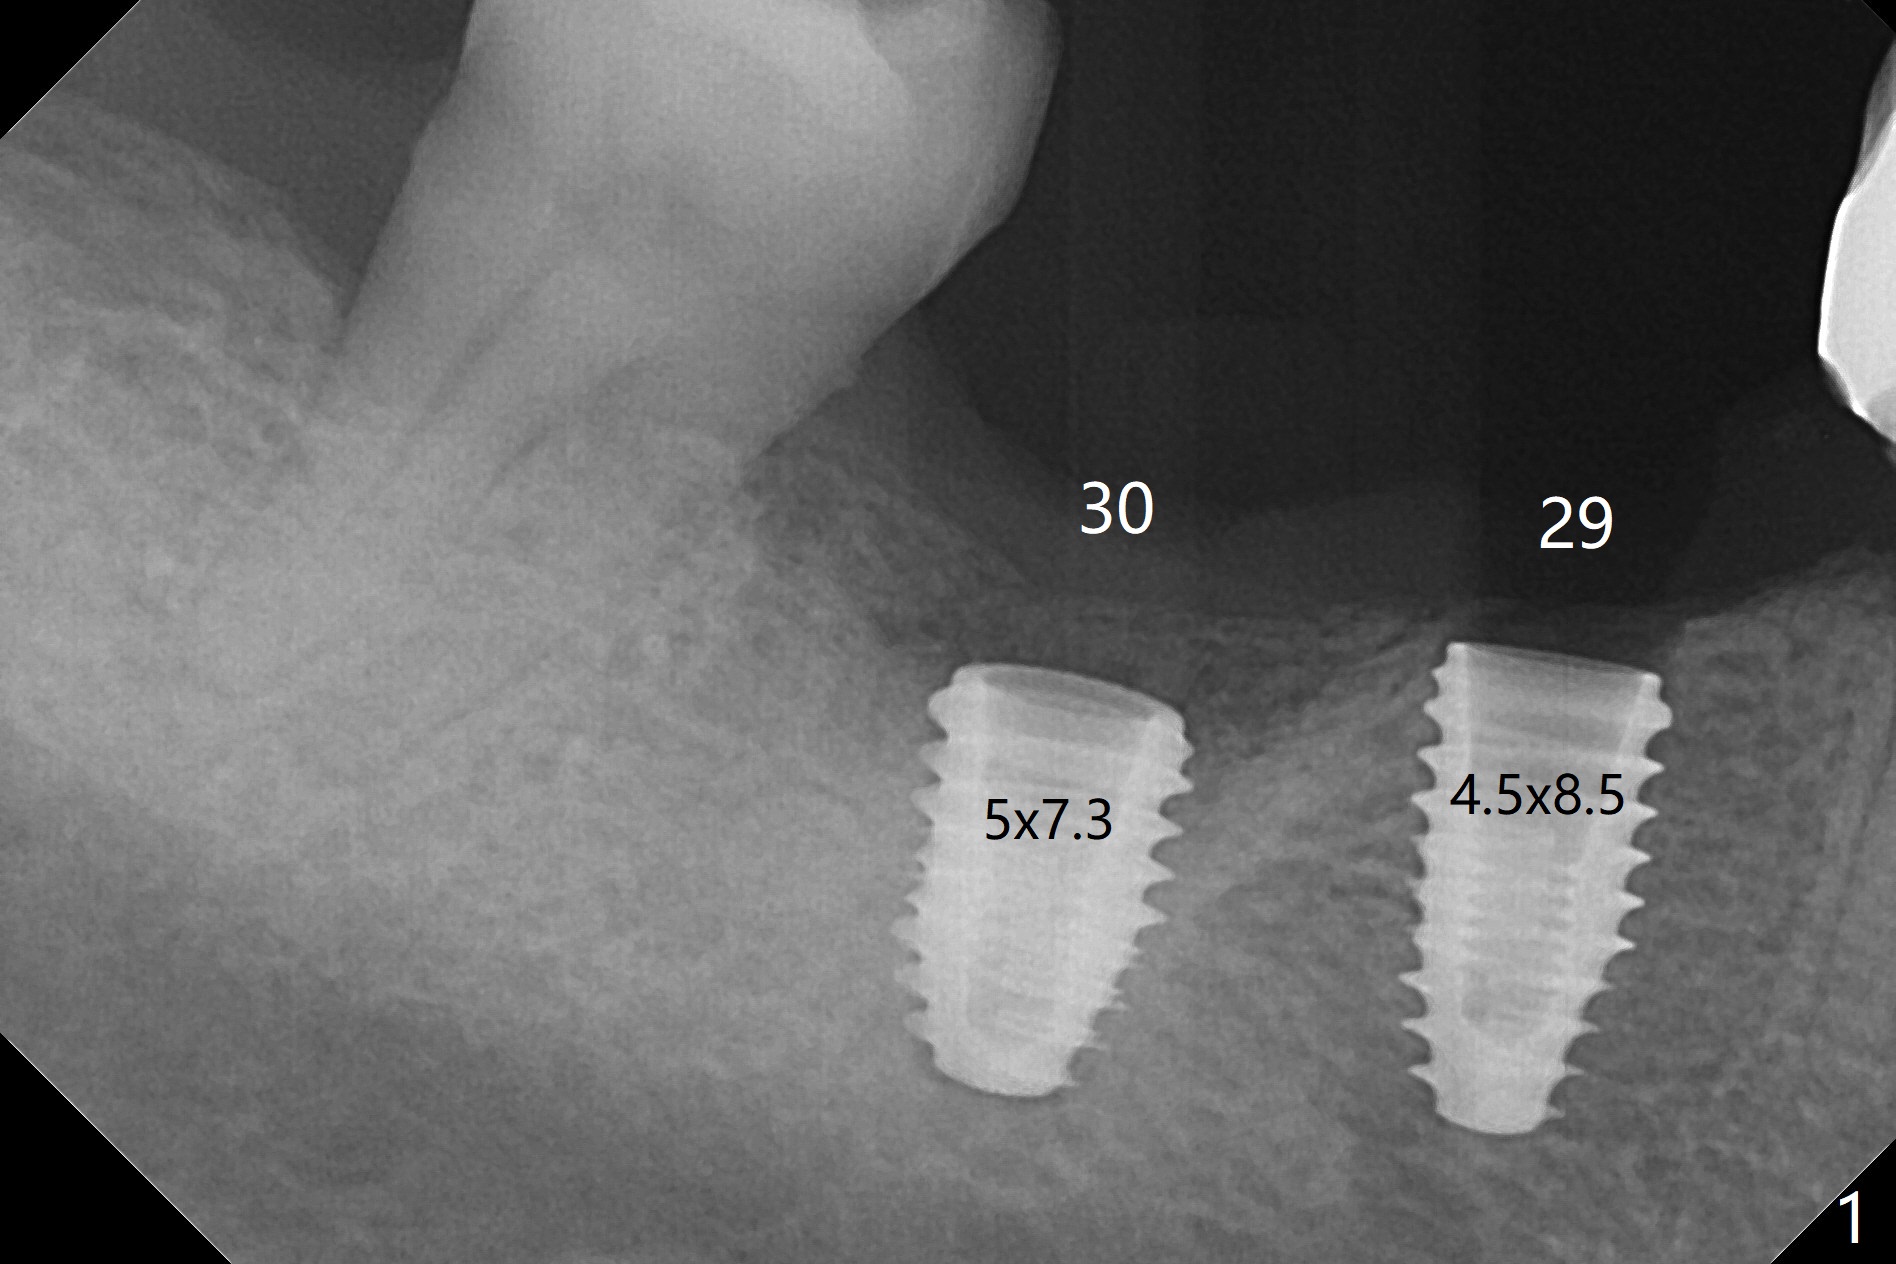

With one carpule of Xylocaine 34 mg with Epinephrine 17 mcg (infiltration) and slow osteotomy with guide, two short implants are placed at #29 and 30 painless with >45 Ncm (Fig.1). Healing abutments are placed without bony interference (Fig.2). It appears that the tooth #31 shifts mesially (Fig.2 arrow), which should be slowed down and/or corrected with early provisional. There is no bone loss 4.5 months postop (Fig.3). With placement of 4.5x4.5(3) and 5.2x4.5(4) mm abutments at #29 and 30, respectively, no limited orthodontic treatment seems to be needed. The screw at #29 becomes loose 4 months post cementation and a few days after #19 implant is loose (bruxism). In fact this is not completely true, since the abutment at #29 is incompletely seated (Fig.4). The abutment at #30 is also incompletely seated because of the vertical gap (<), probably due to mesial and distal crestal interference (*).